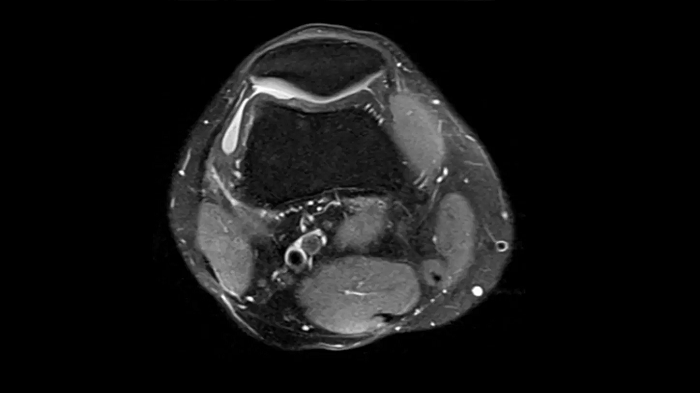

Knee

PD TSE Fat Sat with Deep Resolve and Simultaneous Multi-Slice

For clear imaging of the knee, outstanding fat suppression and performance are possible. Integrating the influence of Deep Resolve with the established Simultaneous Multi-Slice technique.

SMS 2 | Deep Resolve Gain & Sharp

0.4 x 0.4 x 3.0 mm2

TA 2:56 minutes

MAC-ID: 7aaaa0198. Image Credit: Siemens Healthineers

For clear imaging of the knee, brilliant fat suppression and performance are possible. Integrating the influence of Deep Resolve with the proven Simultaneous Multi-Slice technique.

0.3 x 0.3 x 3.0 mm2

TA 2:16 minutes